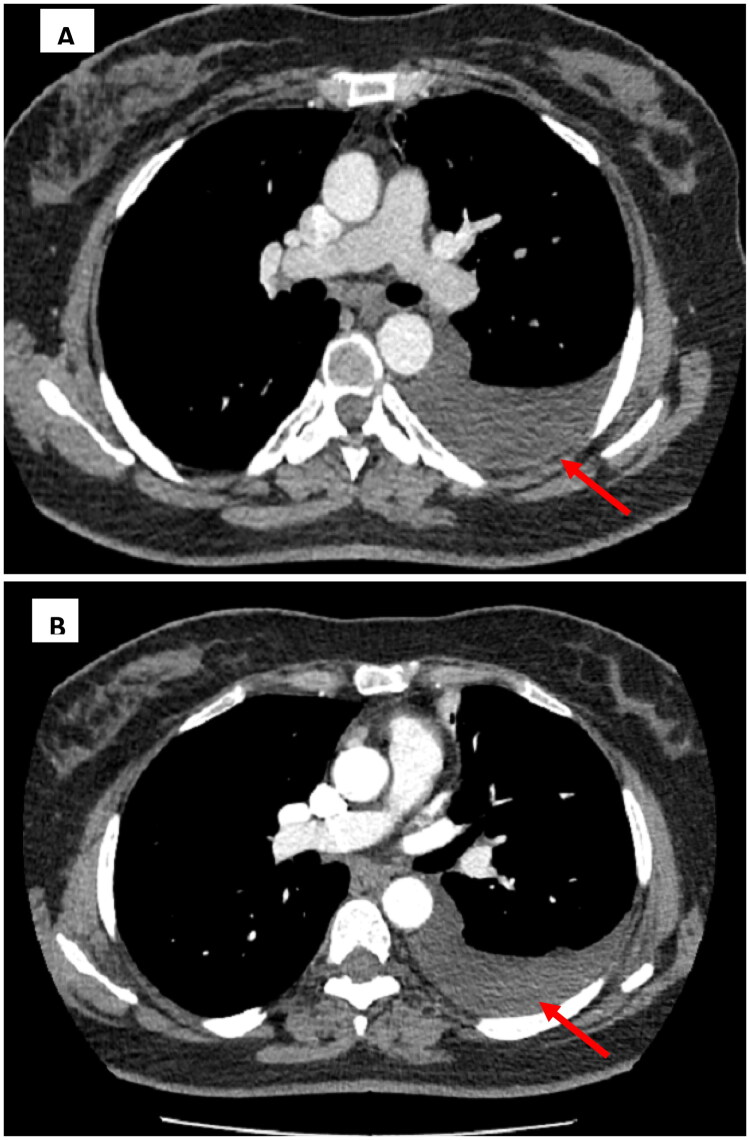

Chylothorax is an uncommon cause of pleural effusion, most often associated with malignancy, trauma, or thoracic duct obstruction. Its occurrence following SARS-CoV-2 infection is exceptional. The present case report describes a 53-year-old woman who was admitted to the pneumology department complaining of chronic dry cough with a medical history of type II diabetes and SARS-CoV-2 infection one month ago. Physical examination revealed decreased vesicular breath sounds at the left lung base. A chest X-ray revealed a left pleural effusion and thoracentesis confirmed chylothorax. This case highlights chylothorax as a rare but possible complication of COVID-19, potentially caused by inflammation and thoracic duct disruption in the absence of thrombosis. It emphasizes the importance of considering chylothorax in the differential diagnosis of unexplained pleural effusions following SARS-CoV-2 infection.